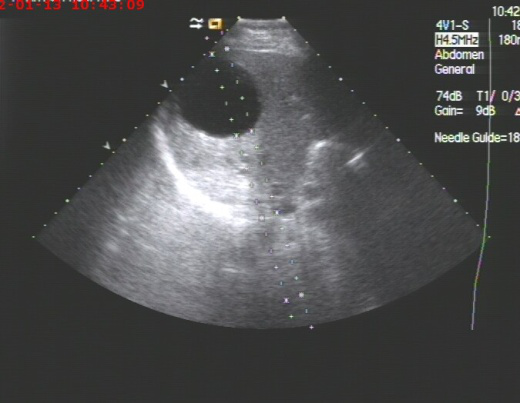

2019年10月呼吸科收治一男性、83岁高龄肺炎合并巨大肝脓肿患者,病人高烧不退,各项感染指标超高,病人既往是多囊肝病人,于10月17日进行超声引导下巨大肝脓肿抽吸治疗术。超声检查局部肝脓肿测量内经达:14cm,术中抽吸灰白色脓液800ml,并送培养,经一个多小时抽吸注药,直至抽出液体清亮,脓肿完全缩小,当即病人病情缓解,高烧消退。送检后显示感染细菌为克雷白氏杆菌,一周后原脓肿再次穿刺治疗,抽出囊液400ml,再次冲洗治疗,经培养已无细菌,随后痊愈出院。